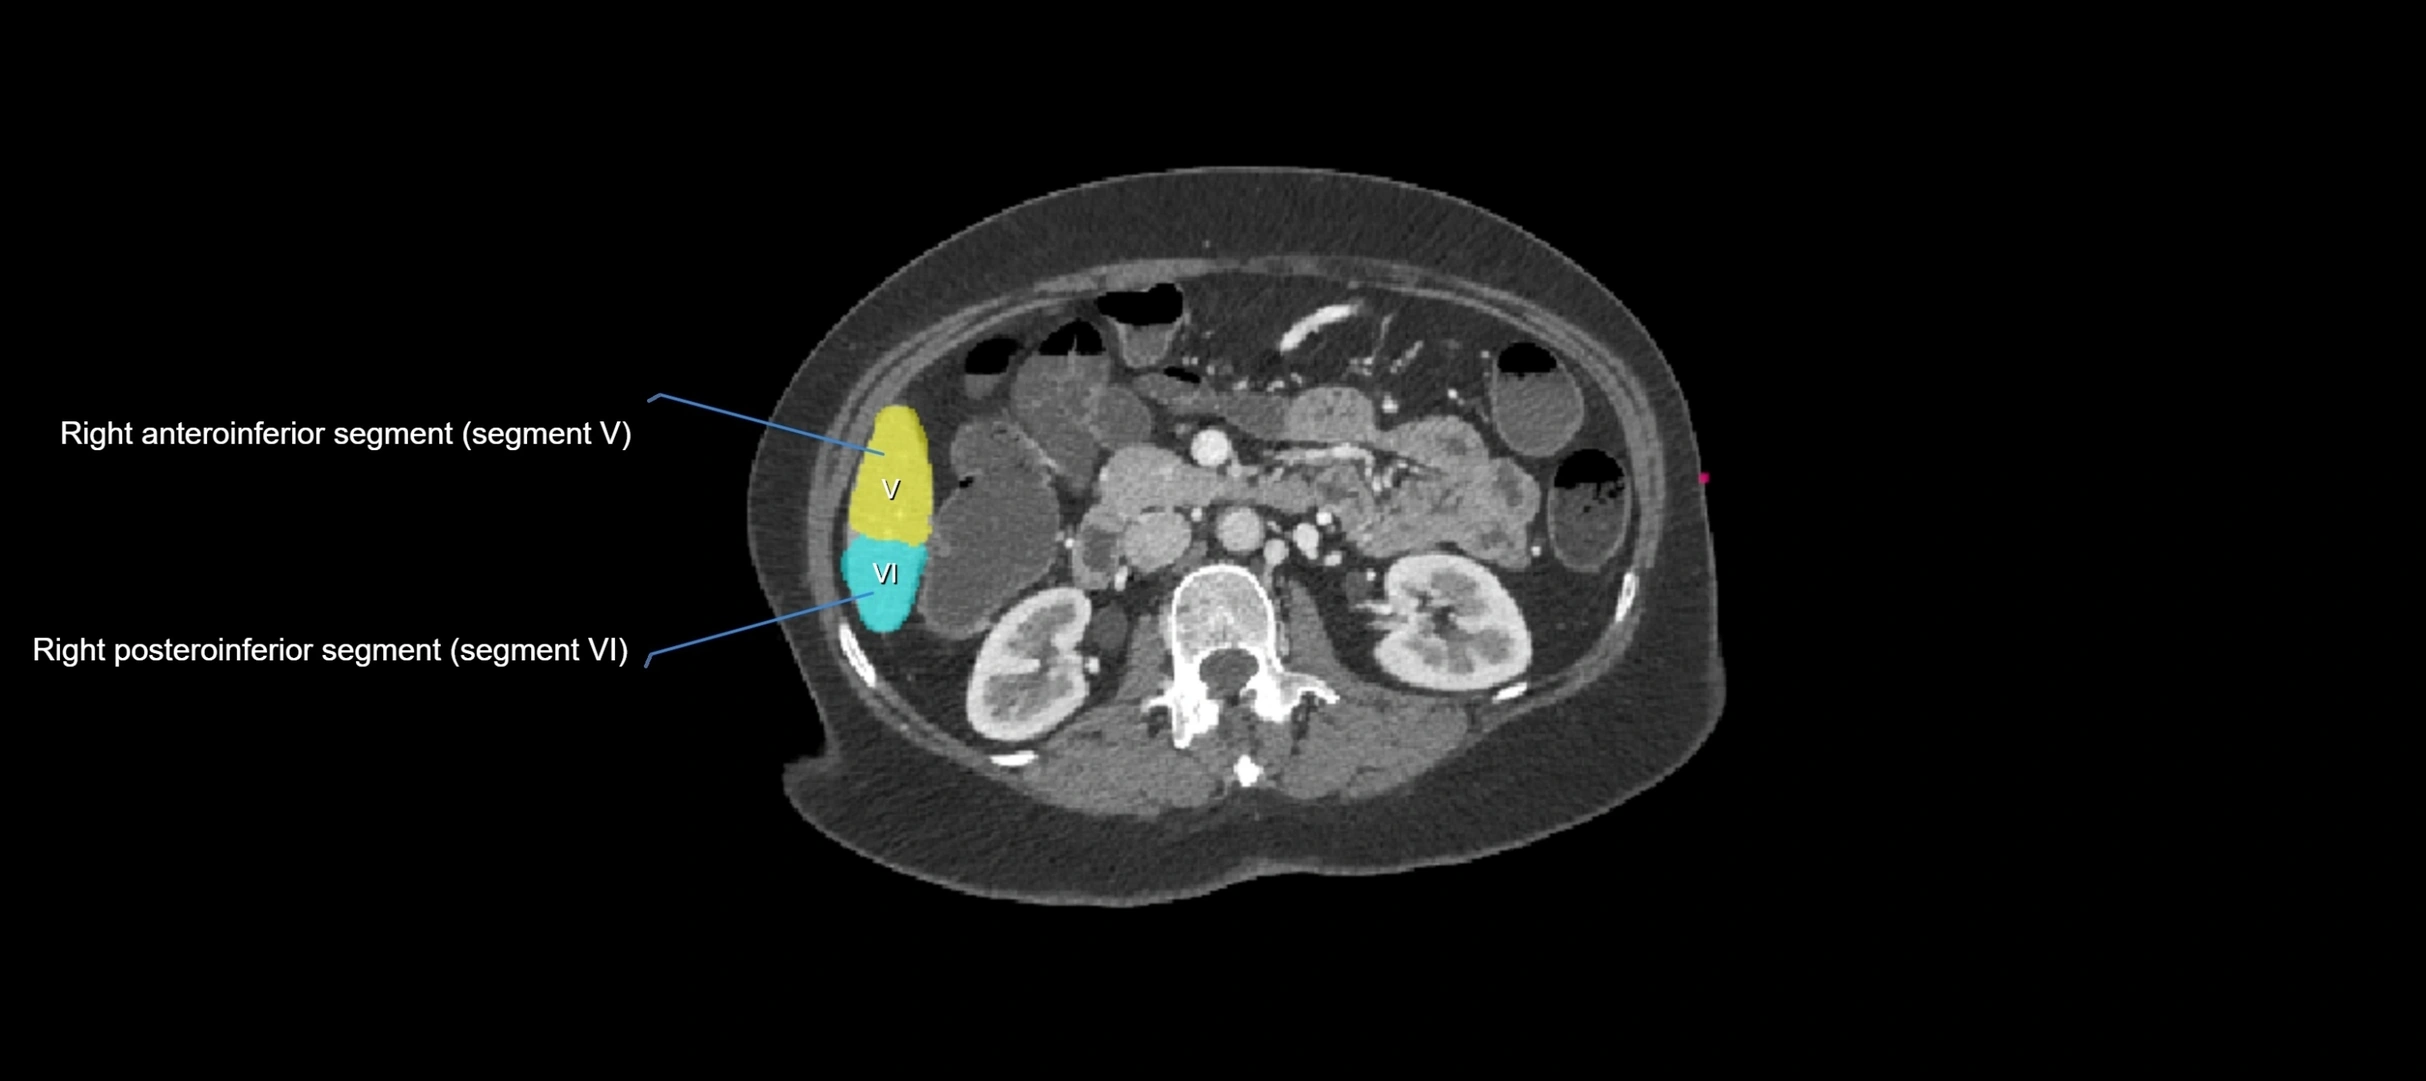

CT Appearance

CT Pre-Contrast:

• Caudate lobe appears as a soft-tissue density, isodense to the rest of the liver

• Enlargement may be appreciated in cirrhosis or Budd–Chiari syndrome

CT Post-Contrast:

• Homogeneous enhancement in the portal venous phase, similar to rest of liver

• Independent venous drainage into the IVC may be visualized

• Lesions follow characteristic CT enhancement patterns (HCC: arterial hyperenhancement with washout; hemangiomas: peripheral nodular enhancement with centripetal fill-in)

CT Venous Phase (functional significance):

• Caudate lobe often enhances relatively more than other lobes in Budd–Chiari syndrome, due to preserved venous outflow

CT Image

image